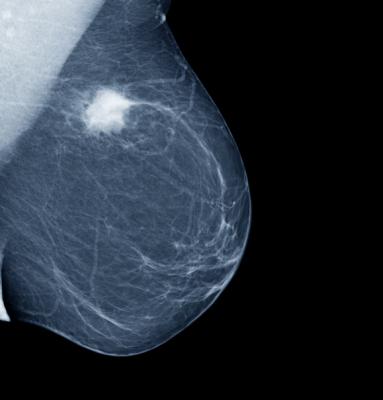

May 11, 2023 — The Radiological Society of North America (RSNA) has announced the results of the RSNA Screening Mammography Breast Cancer Detection AI Challenge. The latest in a series of such research competitions that RSNA has conducted since 2015, this challenge tasked participants with developing artificial intelligence (AI) models that can accurately detect breast cancer from mammography images, potentially assisting radiologists in making more accurate and timely diagnoses.

Breast cancer is the most commonly occurring cancer worldwide, according to the World Health Organization. In 2020 alone, there were 2.3 million new breast cancer diagnoses and 685,000 deaths.

Breast cancer screening has been shown to reduce cancer fatalities. AI tools have the potential to make screening more efficient and effective.